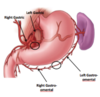

Where does the Upper GI tract end?

Duodenum